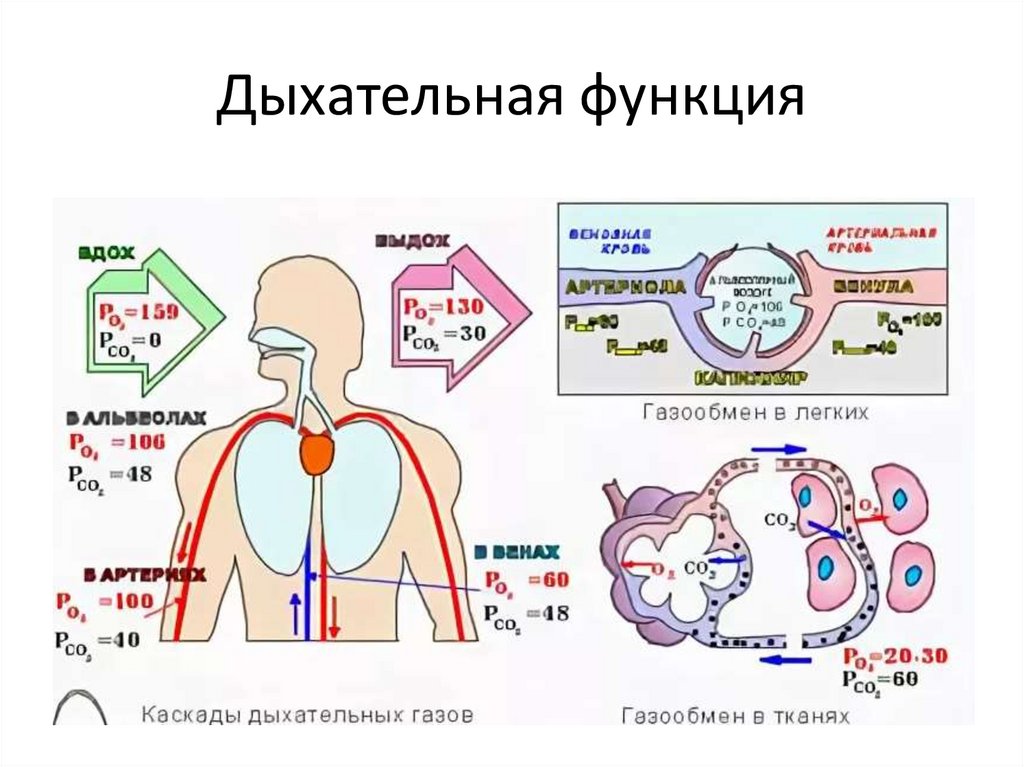

Роль легких в метаболических процессах